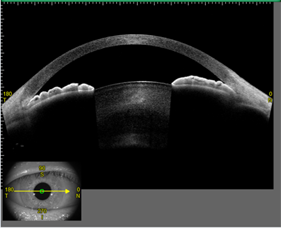

光干渉方式により、前眼部を3D立体画像として非侵襲・非接触で撮影できます。

角膜混濁、円錐角膜などの角膜疾患や狭隅角眼などの術前/術後の検査に威力を発揮します。

また角膜厚や隅角角度などの各種定量解析も正確に行えます。